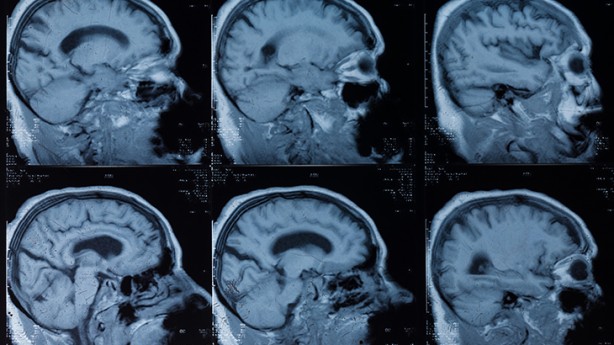

Felç tedavisinde uzmanlaşmış tıbbi personel, hastanın kısa bir klinik geçmişini toplamaya ve genel bir nörolojik muayene yapmaya, eksikliğin ciddiyetini belirli bir ölçek aracılığıyla ölçmeye çalışacaktır. Ayrıca kan testleri, beynin BT taraması ve bazı durumlarda beynin MR'ı çekilir. Doktorlar ayrıca gerekirse EEG gibi başka testler de yapabilirler.